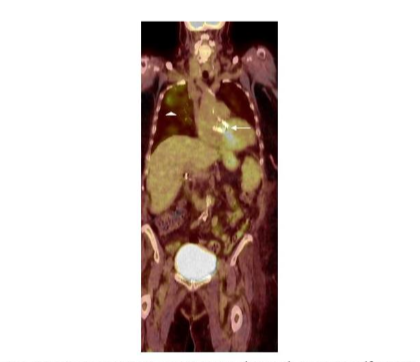

Published data indicate that ¹⁸F-FDG is of value for diagnosing cardiovascular infections. The test is a useful adjunct for diagnosing infective endocarditis with a pooled sensitivity and specificity of 61% and 88%, respectively. It is especially useful in patients with prosthetic heart valves (Figure 13).

Figure 13.

Infected prosthetic aortic valve (arrow). Note the ¹⁸F-FDG accumulation in the right upper lung (arrowhead), which was unsuspected pneumonia. This would not have been diagnosed on echocardiography.